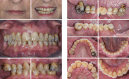

Figures